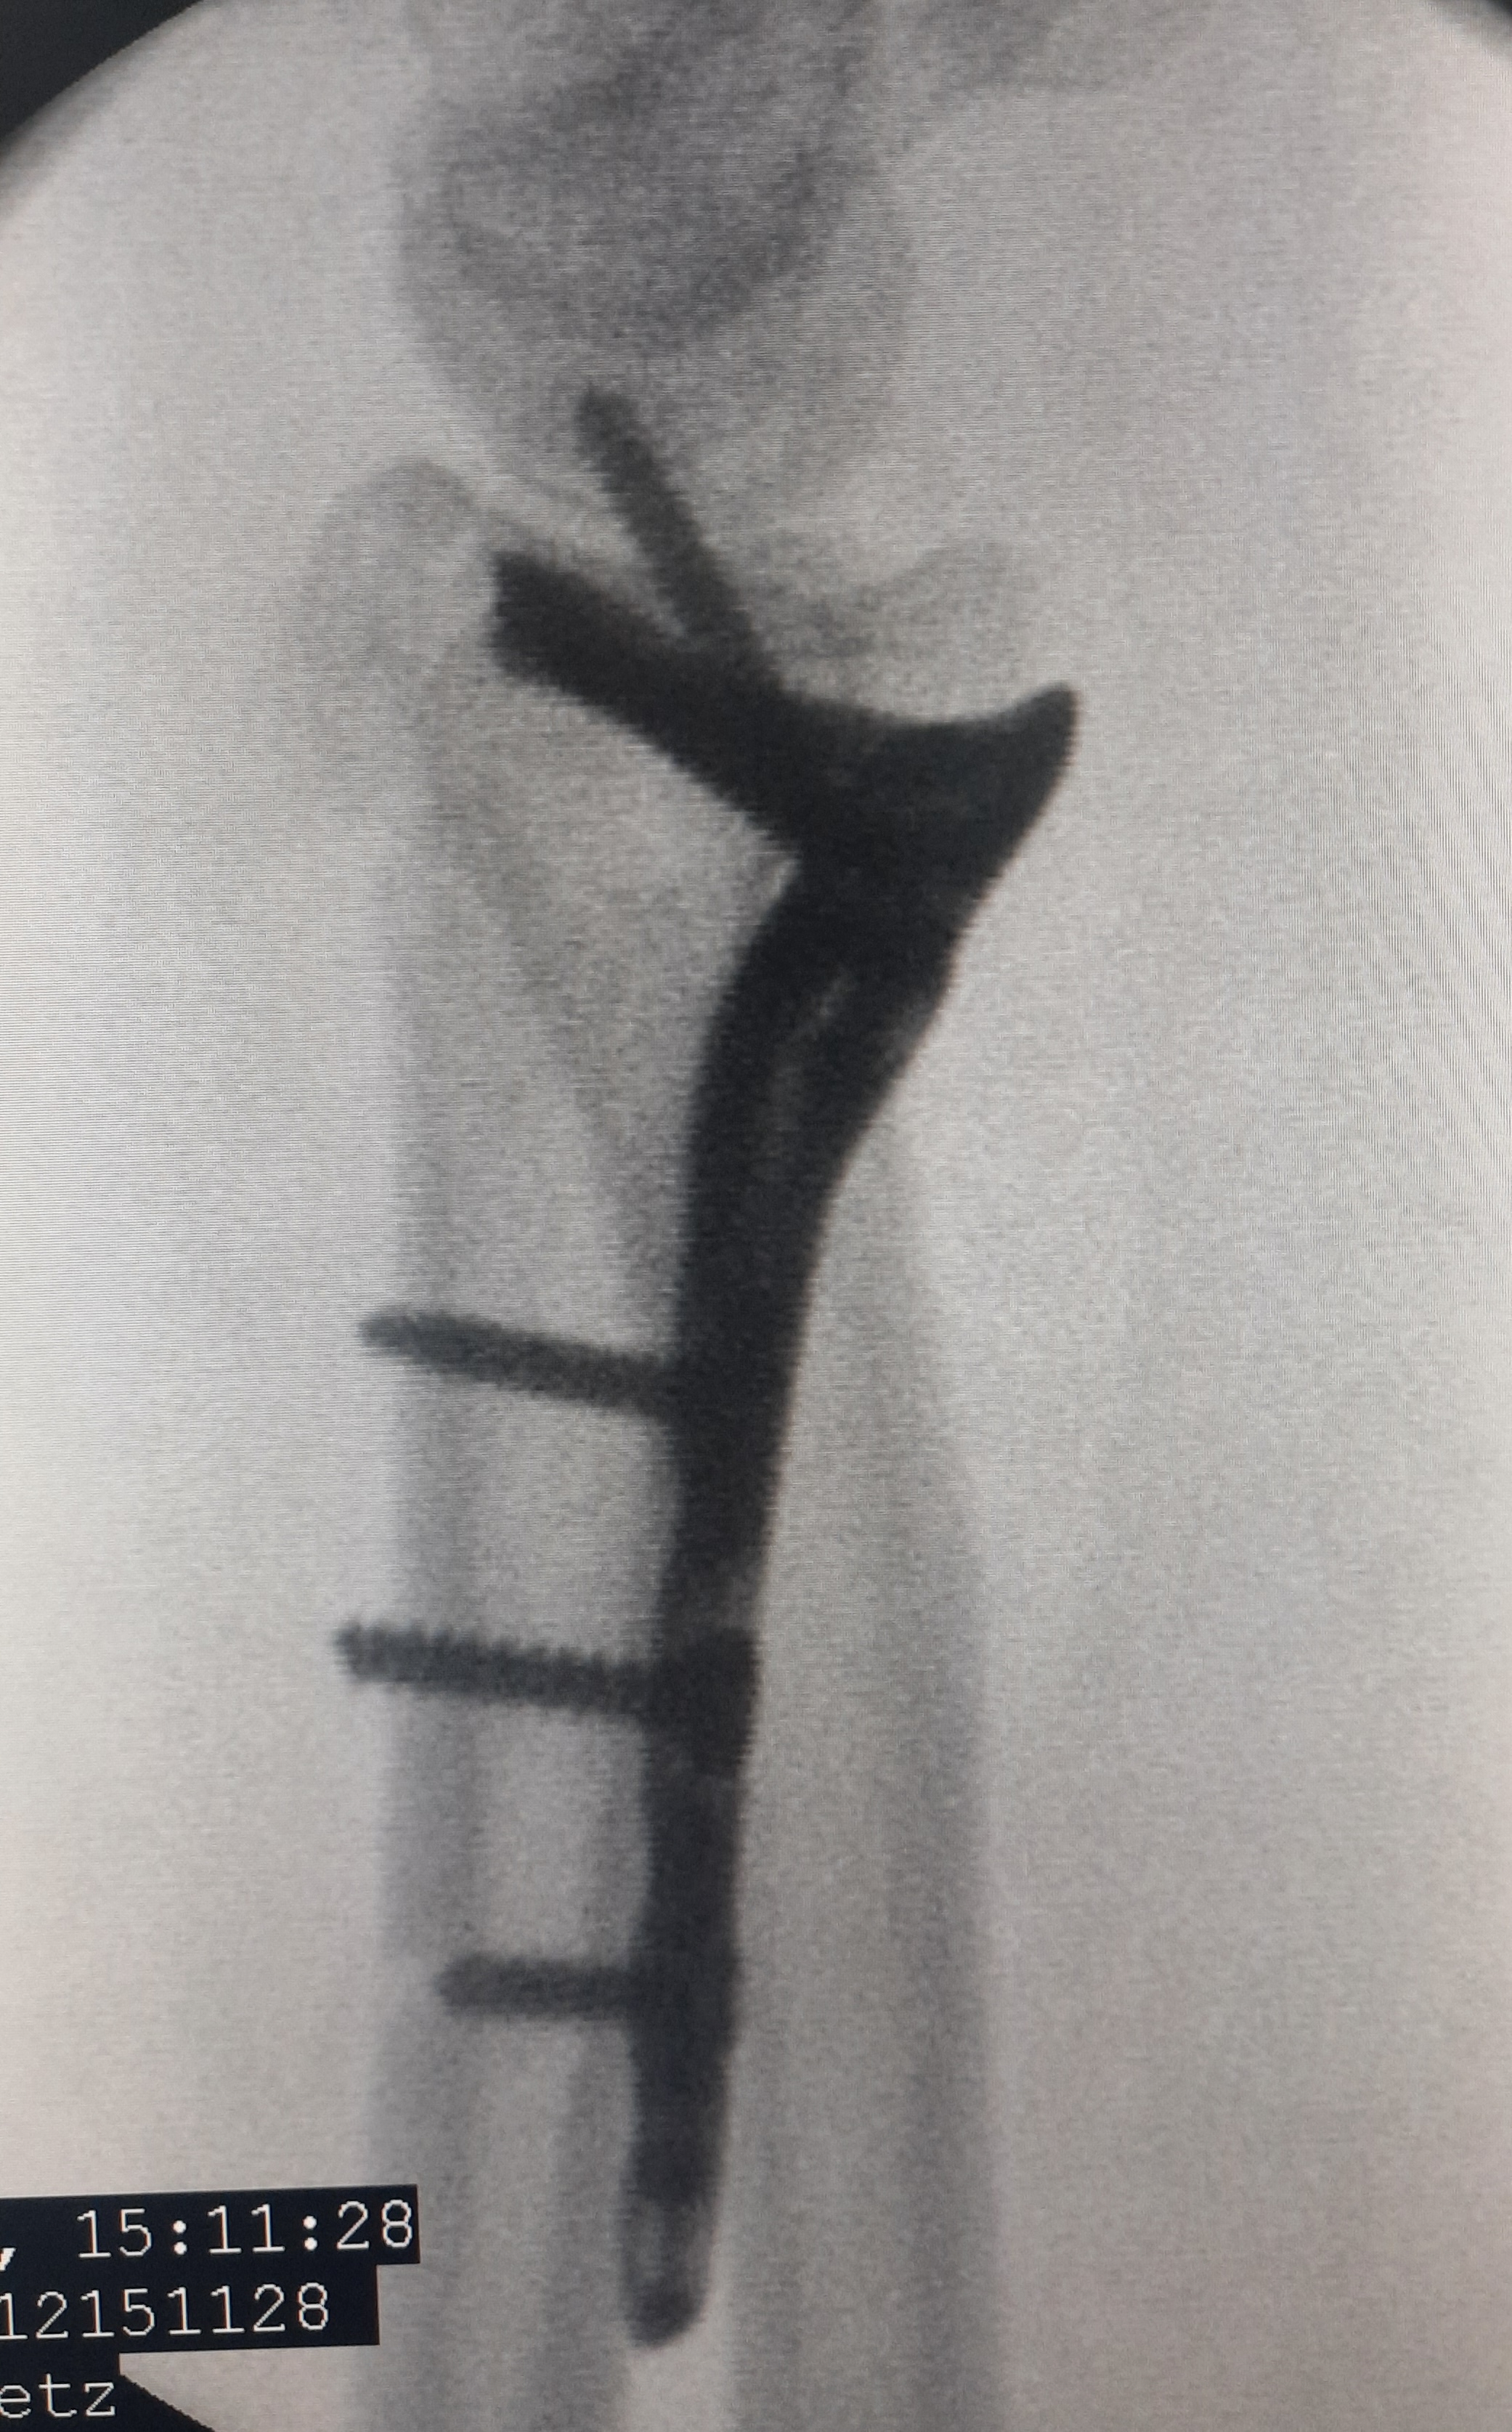

Клинический случай: внутрисуставной перелом дистального метаэпифиза лучевой кости — операция (остеосинтез пластиной)

Этап остеосинтеза: доступ, фиксация и контроль положения пластины.